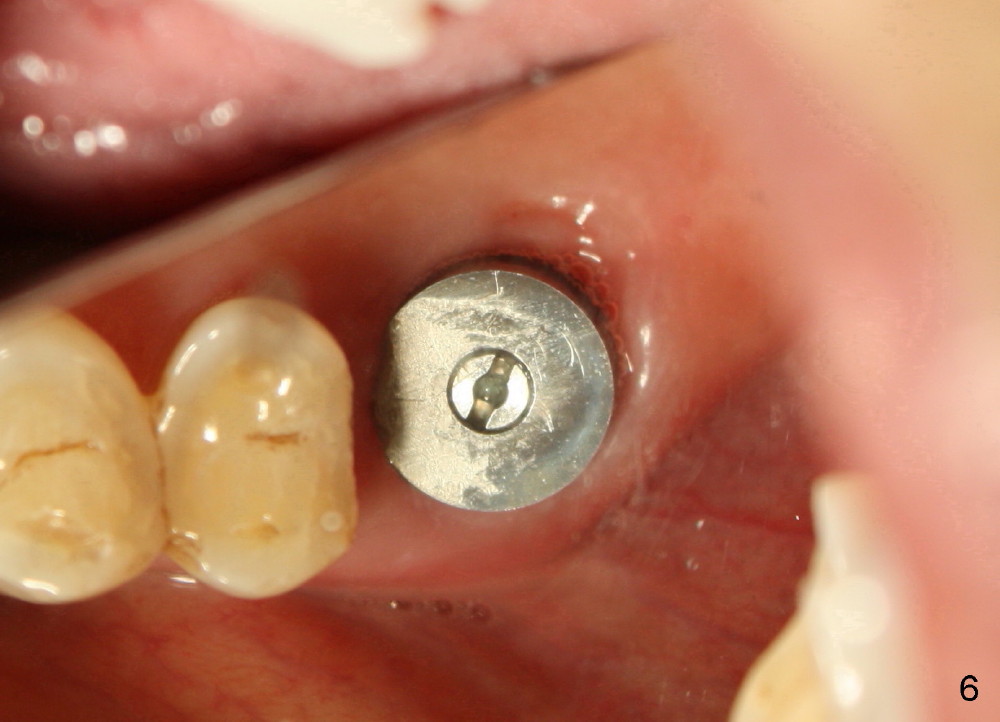

The tooth #14 of a 79-year-old lady is also non salvageable (Fig.4), but this patient chooses immediate implant (Fig.5, 8x14 mm, no bone graft). The socket heals uneventfully (Fig.6, 2 weeks postop). The implant has been in function for 11 months.